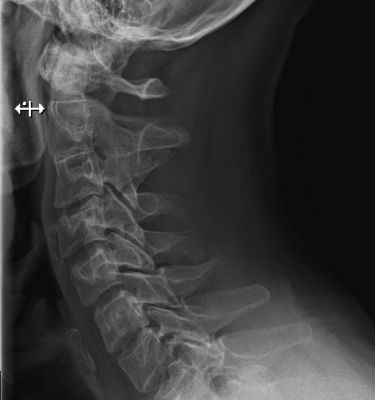

- Остеохондроз шейного отдела позвоночника – дегенеративно-дистрофический процесс.

- Остеофитоз – изменение формы позвонков с образованием остеофитов.

- Межпозвоночная грыжа.

- Протрузия диска шейного отдела.

- Шейный спондилез.

Диагнозы устанавливаются на основе МРТ или КТ шейного отдела, УЗИ сосудов головы и шеи, осмотра врача и проведения тестов.